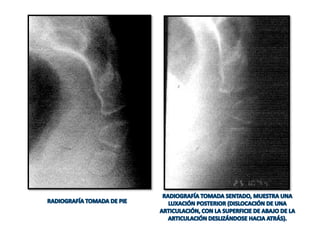

(B) SENTADO:

1) FLEXIÓN: movimiento del coxis en dirección anterior. Es una función

pasiva secundaria a la presión del asiento sobre el coxis.

2) EXTENSIÓN: movimiento del coxis en dirección posterior. Es también una

acción pasiva secundaria a un aumento de la presión del asiento sobre el

contenido pelviano y abdominal.